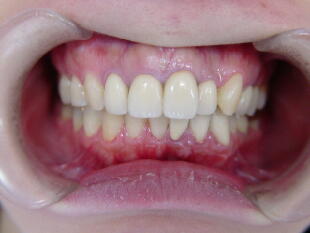

B、部分矯正の後、セラミック冠で治療した症例(上顎前歯部のみ治療)

![]() ![]() ![]()

奥歯のかみ合わせは比較的問題なかったので上の主訴のみ治療。上の前歯を治療するこ

とによって下の前歯も自然に良い位置に移動しました。歯並びを改善することにって歯肉 状態も改善されたことに注目してください。